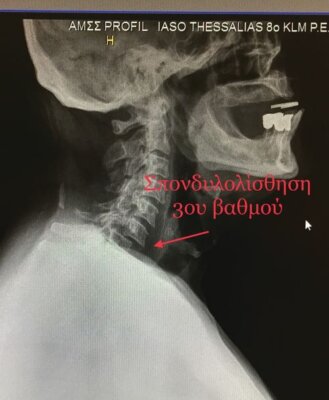

Οι τραυματικές δισκοκήλες δημιουργούνται γενικά μετά από κακώσεις και έχουν ως αποτέλεσμα τον τραυματισμό – ρήξη συνδεσμικών στοιχείων του αυχένα, κάταγμα του σπονδύλου ή σπονδυλολίσθηση.

Η διαγνωστική προσέγγιση γίνεται κυρίως με την κλινική εξέταση και την διενέργεια απεικονιστικών εξετάσεων. Η απλή ακτινογραφία και η αξονική τομογραφία δίνουν πληροφορίες για τις οστικές δομές ενώ η μαγνητική τομογραφία απεικονίζει καλύτερα τα μαλακά μόρια (μεσοσπονδύλιους δίσκους, συνδέσμους, νωτιαίο μυελό και νωτιαίες ρίζες). Ο νευροφυσιολογικός έλεγχος (ηλεκτρομυογράφημα, ταχύτητες αγωγής κ.α.) διενεργείται στις περιπτώσεις στις οποίες πρέπει να αποκλειστεί περιφερική βλάβη η οποία μπορεί να συνυπάρχει.